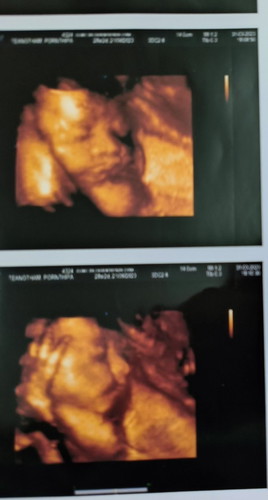

ซาวด์4มิติ

กำหนดคลอด 21 มิย. ค่ะ ได้ลูกชาย ตอนนี้ 29W2D ค่ะ เมื่อเสาร์ที่แล้วไปหาคุณหมอ คุณหมอบอกเด็กน้อย นน.เยอะกว่าเด็กที่อยุ่ในวีคเดียวกัน ลุกเรา นน. 1.4 กก. เลยอาจนะคลอดก่อนกำหนด 😅